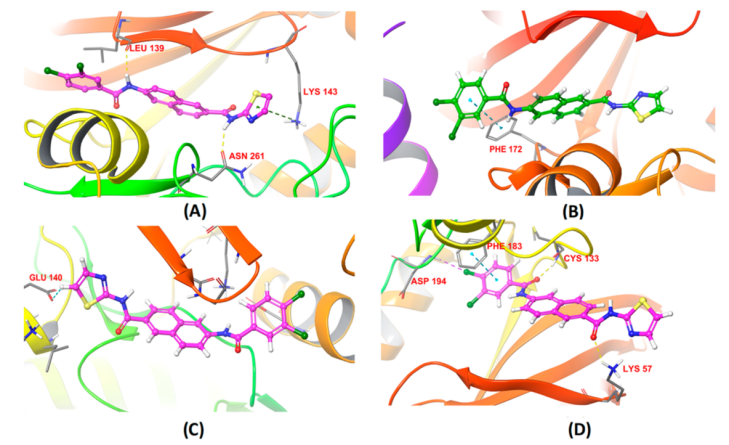

4.3.7 蛋白-小分子对接确定活性位点

在分子动力学模拟中,蛋白-小分子对接是一种常用的技术,用于预测小分子(例如药物分子)如何与蛋白质(例如酶或受体)相互作用。这种相互作用通常发生在蛋白质的活性位点,这是蛋白质上的一个区域,可以与小分子结合,从而影响蛋白质的功能。

对接过程通常涉及以下步骤:

首先,需要知道蛋白质的三维结构。这可以通过实验方法(如X射线晶体学或核磁共振)确定,或者使用计算方法预测。

然后,使用对接软件将小分子“对接”到蛋白质的可能的活性位点。这通常涉及计算不同的小分子姿态和位置,以及它们与蛋白质的相互作用能量。

对接结果通常会产生多个可能的小分子-蛋白质复合物。这些复合物然后可以根据他们的相互作用能量进行排名,以识别最可能的结合模式。

最后,可以使用分子动力学模拟来进一步研究小分子-蛋白质复合物的动态行为。这可以提供关于结合过程的详细信息,例如结合的稳定性,以及小分子和蛋白质之间的详细相互作用。

这些信息对于理解小分子如何影响蛋白质的功能,以及设计新的药物分子具有重要的价值。